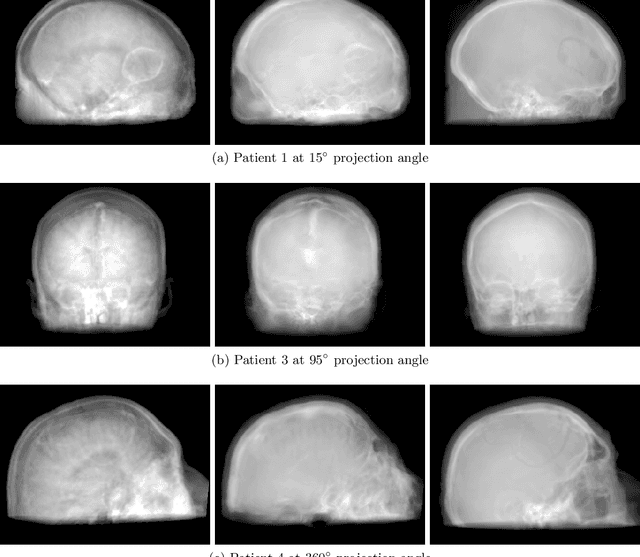

Abstract:Hybrid imaging promises large potential in medical imaging applications. To fully utilize the possibilities of corresponding information from different modalities, the information must be transferable between the domains. In radiation therapy planning, existing methods make use of reconstructed 3D magnetic resonance imaging data to synthesize corresponding X-ray attenuation maps. In contrast, for fluoroscopic procedures only line integral data, i.e., 2D projection images, are present. The question arises which approaches could potentially be used for this MR to X-ray projection image-to-image translation. We examine three network architectures and two loss-functions regarding their suitability as generator networks for this task. All generators proved to yield suitable results for this task. A cascaded refinement network paired with a perceptual-loss function achieved the best qualitative results in our evaluation. The perceptual-loss showed to be able to preserve most of the high-frequency details in the projection images and, thus, is recommended for the underlying task and similar problems.